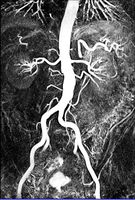

Häufigste Erkrankung der Aorta ist eine Ausweitung bzw. Aussackung in einem bestimmten Bereich (Aortenaneurysma). Diese Erkrankung bedroht das Leben der betroffenen Patienten, da die Hauptschlagader im betroffenen Abschnitt platzen kann, was zur inneren Verblutung führt. Aneurysmen können in allen Abschnitten der Aorta vorkommen.

Eine Sonderform des Aneurysmas stellt die Aortendissektion dar. Bei diesem akut auftretenden, lebensbedrohlichen Krankheitsbild kommt es zu einer Einblutung in die Wandschichten der Aorta. Dies kann u.a. zum Zerreißen der Aortenwand und zu Durchblutungsstörungen der inneren Organe (Herz, Gehirn, Darm, Niere, etc.) führen. Ist der herznahe Abschnitt der Aorta betroffen, muss sofort eine Operation erfolgen.

Bei der Operation wird der erkrankte Abschnitt der Aorta durch eine Gefäßprothese (Kunststoffschlauch) ersetzt . Bei der katheterbasierten Therapie wird das Aneurysma von innen mit einer Gefäßstütze (Stent) geschient. Dieser Eingriff ist wesentlich schonender und kann auch ohne Vollnarkose durchgeführt werden. Beide Verfahren haben Vor- und Nachteile. Die Frage, welches Verfahren für den einzelnen Patienten das beste ist, muss abhängig von den Befunden und dem Befinden der Patienten beantwortet werden.